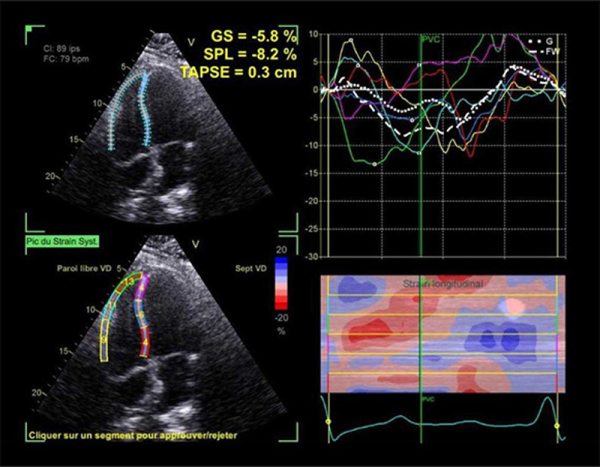

FEVG 35%, hypokinésie diffuse Dégradation de la fonction VD désormais dilaté, Strain paroi libre altérée -8% (TAPSE 19mm, S’ 9cm/s) . IT torrentielle avec inversion du flux systolique de la VSH . Protrusion de la sonde VG (sinus coronaire) au travers du plan de la valve responsable d’une IT laminaire. Pas de participation évidente de la sonde VD.

Prothèse Occluser FOP en place ne semblant pas participer au mécanisme. OD également dilatée.

Figure 2